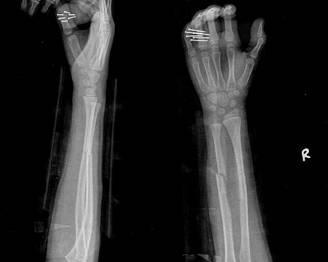

摘要:最新尺橈骨融合方法展現(xiàn)骨頭間的奇妙和諧與友情力量。通過先進的醫(yī)療技術(shù),尺骨和橈骨之間的融合得到顯著改善。這種方法不僅提高了治療效果,還展現(xiàn)了人體骨骼之間的和諧關(guān)系。憑借友情和信念的力量,醫(yī)學界不斷突破,為患者帶來福音。

在醫(yī)生的介紹下,他們了解到了一種最新的尺橈骨融合治療方法——通過微創(chuàng)手術(shù)進行骨骼融合的新技術(shù),這種方法不僅減少了手術(shù)風險,還能更快地恢復(fù)活動能力,雖然小明感到害怕,但他的朋友們一直陪伴在他身邊,給予他勇氣和力量。